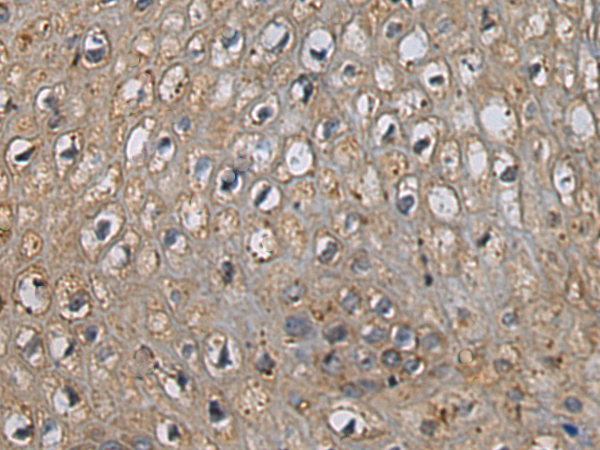

分类: 科研抗体货号: P02243别名: MLN50; Lasp-1应用: WB,IHC反应种属: Human, Mouse, Rat